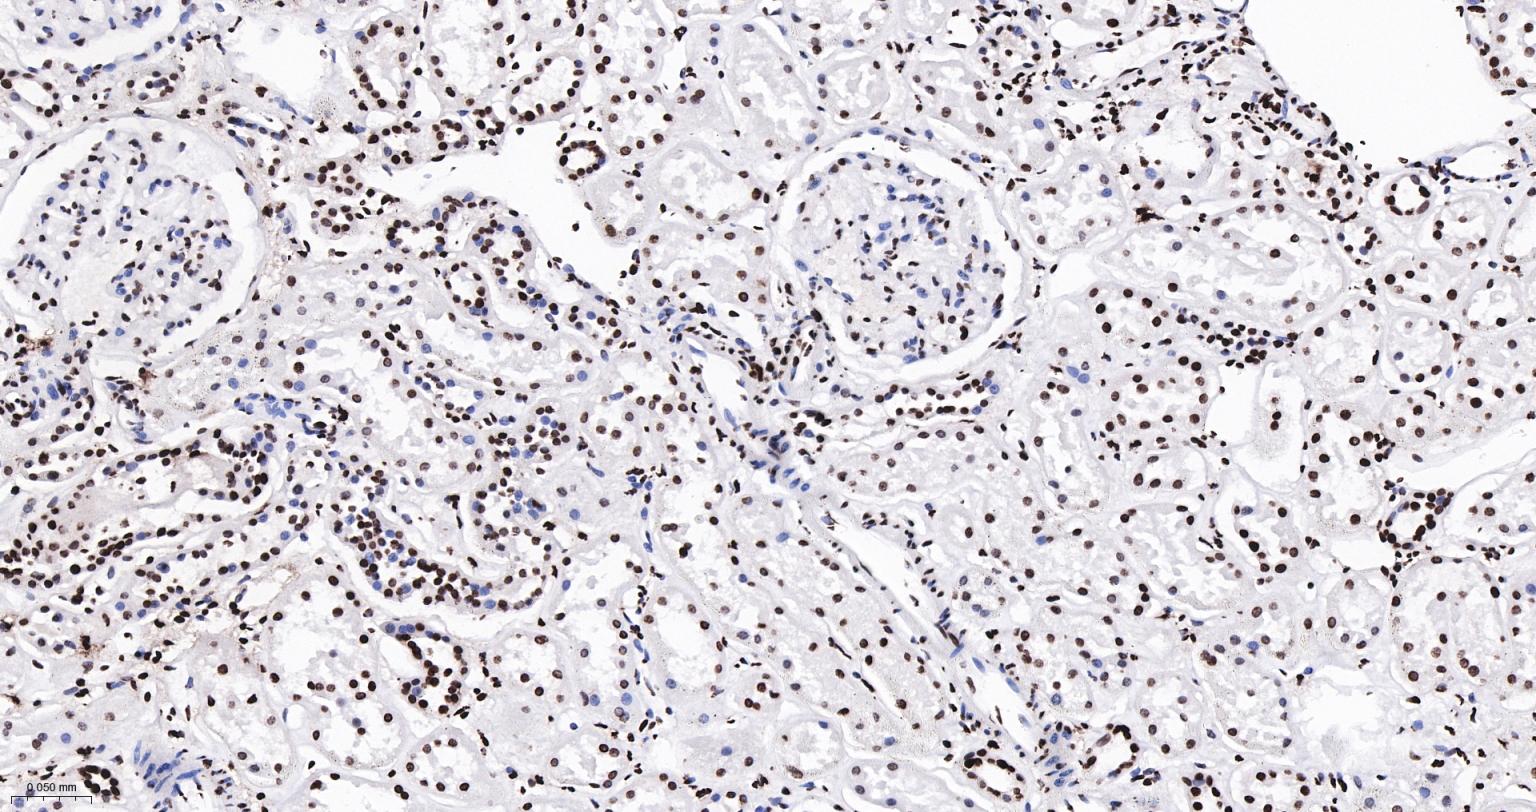

Paraformaldehyde-fixed, paraffin embedded Human Kidney; Antigen retrieval by boiling in sodium citrate buffer (pH6.0) for 15 min; The section was incubated with Acetyl-Histone H3(K9) Monoclonal Antibody, Unconjugated (bsm-63244R) at 1:200 overnight at 4°C, followed by conjugation to the bs-0295G-HRP and DAB (C-0010) staining.

Paraformaldehyde-fixed, paraffin embedded Rat Kidney; Antigen retrieval by boiling in sodium citrate buffer (pH6.0) for 15 min; The section was incubated with Acetyl-Histone H3(K9) Monoclonal Antibody, Unconjugated (bsm-63244R) at 1:200 overnight at 4°C, followed by conjugation to the bs-0295G-HRP and DAB (C-0010) staining.

Paraformaldehyde-fixed, paraffin embedded Mouse Kidney; Antigen retrieval by boiling in sodium citrate buffer (pH6.0) for 15 min; The section was incubated with Acetyl-Histone H3(K9) Monoclonal Antibody, Unconjugated (bsm-63244R) at 1:200 overnight at 4°C, followed by conjugation to the bs-0295G-HRP and DAB (C-0010) staining.